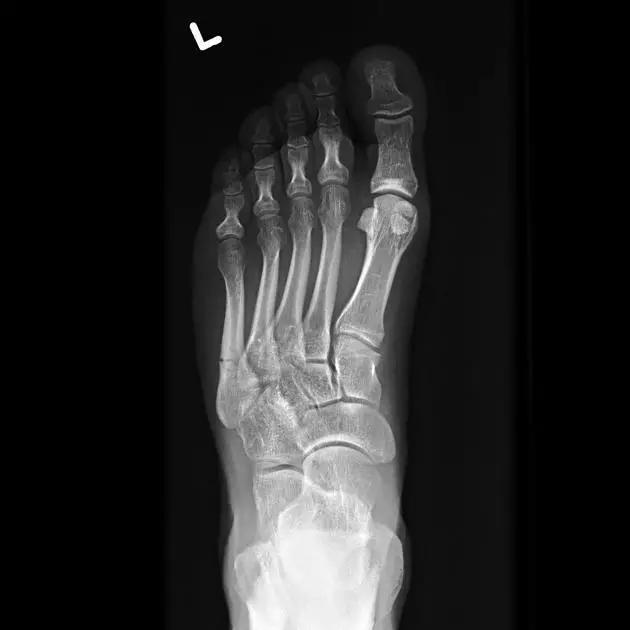

13. Lisfranc 骨折

骨折累及到足的跗骨关节。跖跗关节位于足的前部,是构成足纵弓及横弓的重要结构。

第一跖骨与第一楔骨组成鞍状关节,整个跖跗关节的稳定性,有赖于第一跖跗关节的稳定性,一旦第一跖跗关节发生脱位,其他 4 个跖跗关节容易发生脱位。第一跖跗关节的关节囊有背侧和跖侧副韧带增强,其内缘尚有胫前肌腱附着。第一、二跖骨基部无韧带相连,第一楔骨与第二跖骨基部间有坚韧的 Lisfranc 韧带相连,有助于第一跖跗关节的稳定性。第二楔骨较短,第二跖骨位于第一、二楔骨之间成为外力作用的支点。因此第二跖骨基底易发生骨折。

Lisfranc 关节复合体(Lisfranc joint complex)示意图:first metatarsal 第一跖骨;second metatarsal 第二跖骨;Lisfranc joint 利斯弗朗关节;first,second and third cuneiforms 第一,二,三楔骨;cuboid 骰骨

14.第五跖骨骨折

第五跖骨基底部骨折的不同类型:Stress 骨折;Jones 骨折:第五跖骨基底部以远 1 英寸内的骨折称为 Jones 骨折; Avulsion 骨折。